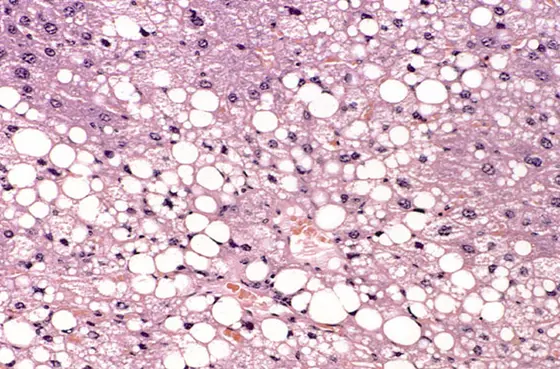

Histological section of a murine liver showing severe steatosis.

Fatty liver disease often leads to chronic liver inflammation and can even result in liver cancer. Scientists from the German Cancer Research Center (DKFZ) and the University of Tübingen have now shown in mice* that intermittent fasting on a 5:2 schedule can halt this development. The fasting regime reduces the development of liver cancer in mice with pre-existing liver inflammation. The researchers identified two proteins in liver cells that are jointly responsible for the protective effect of fasting. An approved drug can partially mimic this effect.

The most common chronic liver condition is non-alcoholic fatty liver disease. It can have serious consequences: If left untreated, it can lead to liver inflammation (metabolic dysfunction-associated steatohepatitis, MASH), liver cirrhosis and even liver cancer. Fatty liver disease is largely considered to be a direct consequence of obesity. It is not only people in Europe and the USA who have put on enormous amounts of weight in recent decades; obesity is also becoming increasingly widespread in emerging countries such as India and China. As a result, the number of cases of liver failure and liver cancer is rising sharply in the countries affected.